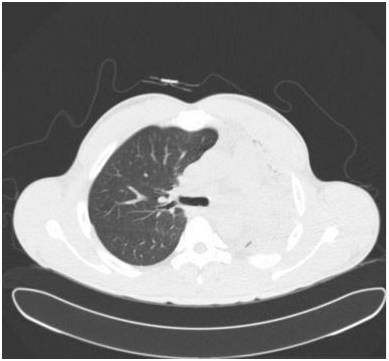

胸部前后位示弥漫不均匀的异常密度影,左肺体积缩小,左肺门区肿块样影与心膈角呈钝角。未增强纵隔窗CT示左肺肺不张,左主支气管完全受阻。增强CT示左主支气管及其段支气管内非强化的肿块。最小密度投影示左肺叶远端支气管重度狭窄,左主支气管及以下层面受阻。